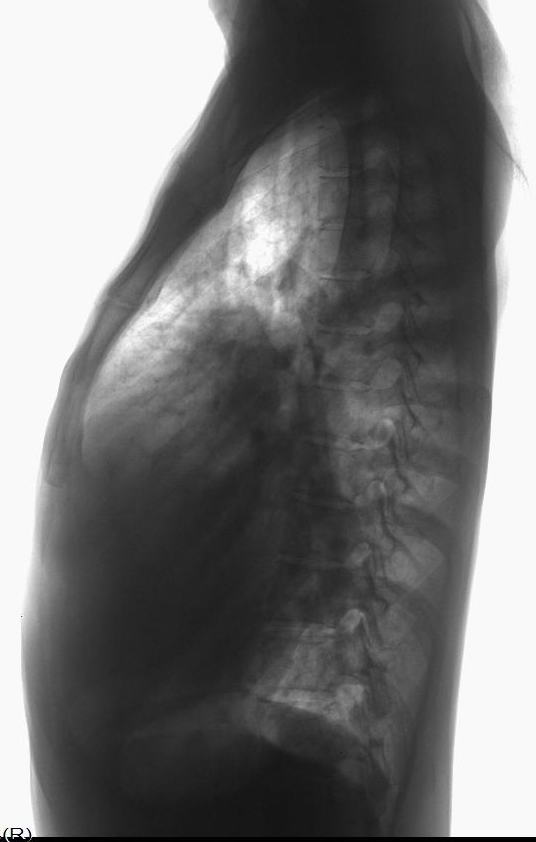

先天性心脏病、房间隔缺损

男31岁,心悸,气短

:主动脉结小,肺动脉突出,左心缘圆隆,右心房/心高值大,未见双房影,双肺呈多血改变,右下肺动脉宽。

符合先心病。心房间隔缺损。建议心彩。